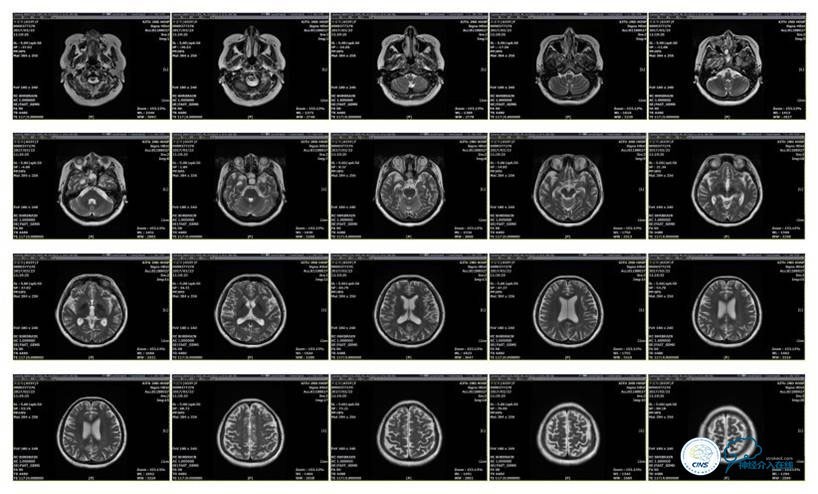

2016-5-19 MRI

2016-05-20 MRV

2016-06-03 CT

2017-06-07 CT

磁共振黑血系列